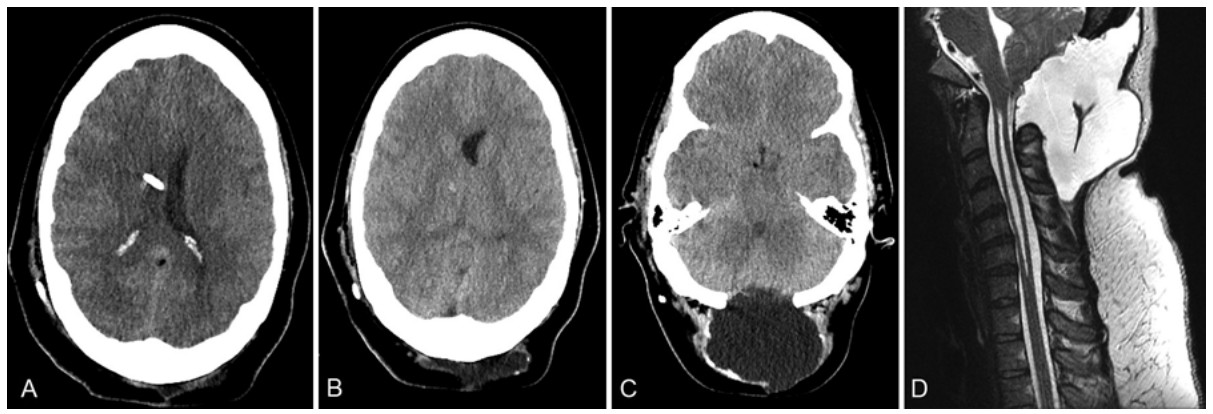

在育龄期女性中,临床上常用左炔诺孕酮释放型宫内节育器(LIUDs)来减少副作用的发生。在这篇文章中,作者提供了一个难治性脑积水伴假性脑膜膨出(PMC)最终得到治疗的病例,这两种病症在LIUD取出后都得到了完全治愈。

一位植入LIUD的35岁女性诊断为Chiari畸形I型,在接受了枕下减压手术治疗后,出现症状性PMC和脑积水。在接下来的8个月中,她接受了脑室腹腔分流手术,并尝试了两次头皮针穿刺减压,但结果是除了很少一段时间的缓解外,她的症状及PMC基本没有得到改善。随后,她接受了LIUD摘除手术。在取出LIUD三周后,在没有任何其他干预的情况下,她的脑积水症状以及脑膜膨出完全消失了。因此,作者得出结论,枕下减压术后颅内压升高和持续性PMC可能部分跟LIUD放置有关。

这个病例表明,在LIUD取出后,跟LIUD相关的问题(PMC及颅内高压)迅速得到缓解。目前已经证实孕激素跟颅内压增高有关,然而,目前没有证据表明LIUDs(局部释放孕激素)和脑积水之间存在联系。LIUDs作为引起颅内高压的原因仍然存在疑问。需要进一步的研究来评估LIUD和颅内高压之间的潜在因果关系。作者建议临床医生在鉴别诊断时考虑到这种情况的可能。

图:Chiari畸形I型后颅窝减压术后2个月出现难治性脑积水、假性脑膜膨出,行V-P分流术后,脑室变小,但假性脑膜膨出依然存在。这些症状在LIUDs取出后得到明显缓解。